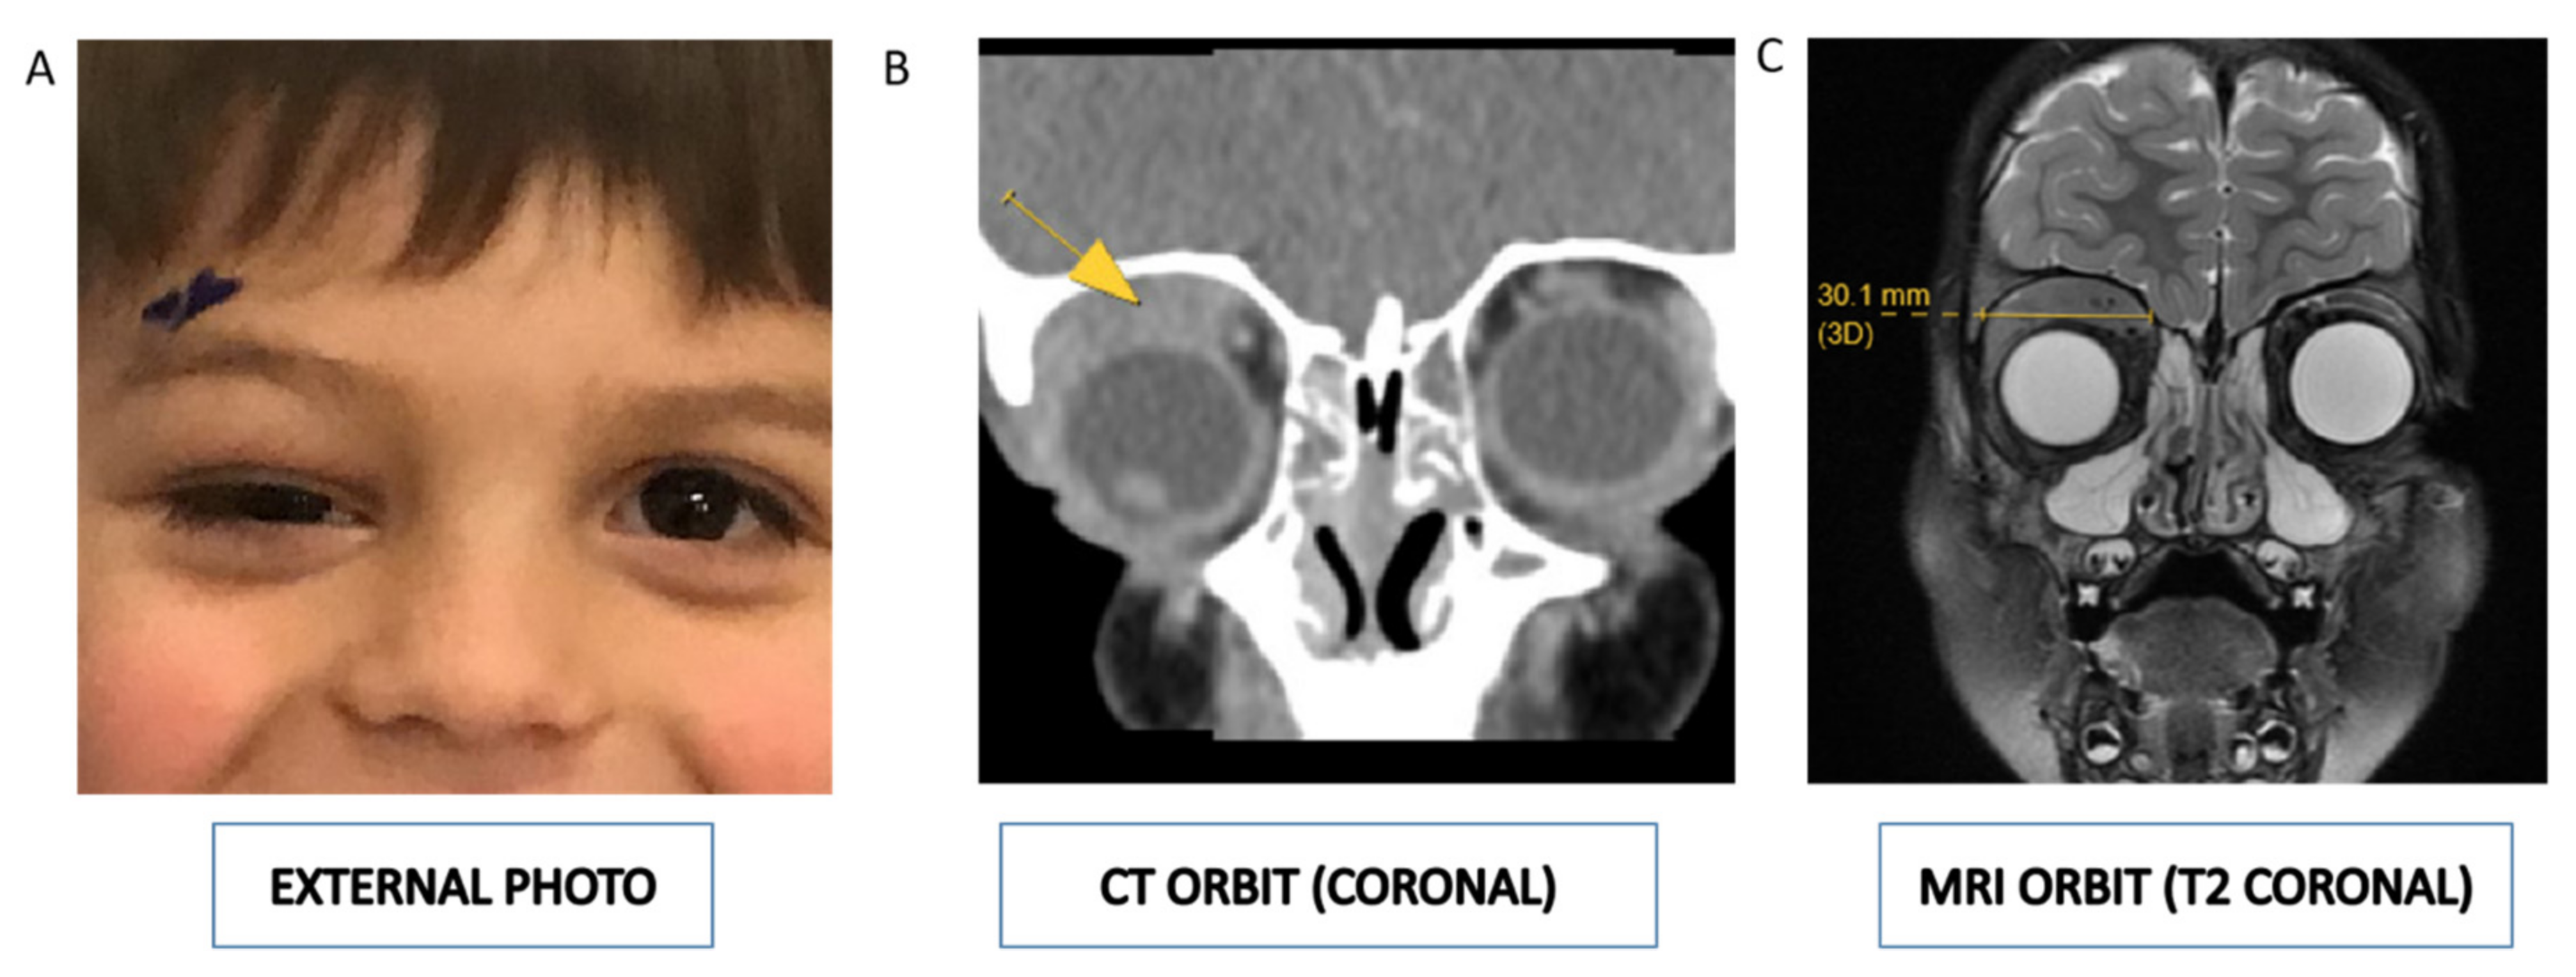

| 8 | 4yrs | M | USA | Superior | R | Eyelid swelling; hypoglobus; ocular motility deficit | None | Orbital mass biopsy; peripheral blood smears; bone marrow aspirate smears; flow cytometry; UCSF500 molecular test (next generation sequencing) |